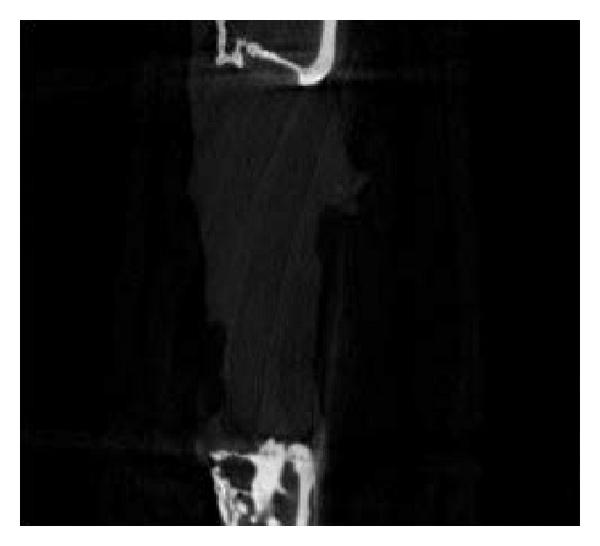

3.4. Micro-CT Examination

Micro-CT examination of 5 rabbits (2 from group A, 2 from group B, and 1 from group C) was conducted 3 months after surgery. The shapes of the rabbit bones at 3 months were shown in Figure 4. The bone defect in group A was not completely repaired, which in group B was completely repaired, while group C showed typical bone nonunion. The number of trabeculae per mm in groups A, B, and C was 0.40, 0.17, and 0.34, respectively. The bone mineral density in groups A, B, and C was 1.25434 mg/cc, 1.32521 mg/cc, and 1.3349 mg/cc, respectively, and the high bone density in group C resulted from osteosclerosis. The mass losses of PLLA and PLLA/PCL were 63.575% and 67.195%, respectively. These two scaffolds have fast initial degradation rate and then slowed down and cannot completely degrade 3 months after implantation.

(a)

(b)

(c)

(d)

(e)

(f)

(g)

(h)

(i)